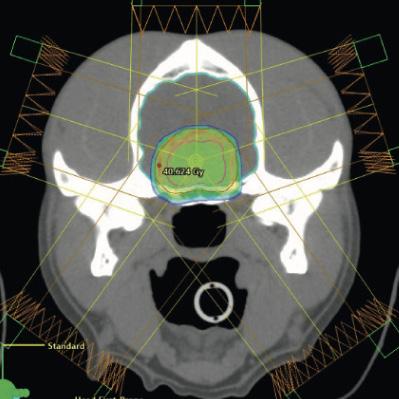

View of a radiation plan of two patients with pituitary tumors. The image at the top shows a regular irradiation protocol with a mean dose of 10x4 Gy; the image at the bottom shows the “boost” dose in the tumor center mentioned in the text with 15 percent more dose.